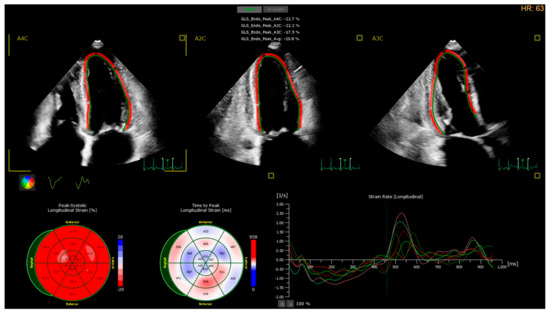

3. Cirrhotic Cardiomyopathy Diagnostic Approach with Echocardiography: Current Knowledge

4. Cirrhotic Cardiomyopathy Diagnostic Approach with Echocardiography: Future Perspectives

- Sampaio, F.; Pimenta, J.; Bettencourt, N.; Fontes-Carvalho, R.; Silva, A.P.; Valente, J.; Bettencourt, P.; Fraga, J.; Gama, V. Systolic and diastolic dysfunction in cirrhosis: A Tissue-Doppler and speckle tracking echocardiography study. Liver Int. 2013, 33, 1158–1165. [Google Scholar] [CrossRef]

- Rimbaş, R.C.; Baldea, S.M.; Guerra, R.D.G.A.; Visoiu, S.I.; Rimbaş, M.; Pop, C.S.; Vinereanu, D. New Definition Criteria of Myocardial Dysfunction in Patients with Liver Cirrhosis: A Speckle Tracking and Tissue Doppler Imaging Study. Ultrasound Med. Biol. 2018, 44, 562–574. [Google Scholar] [CrossRef] [PubMed]